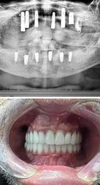

علاج الزرع السني

تطبيقات البورسلين

تطبيقات الزركونيوم